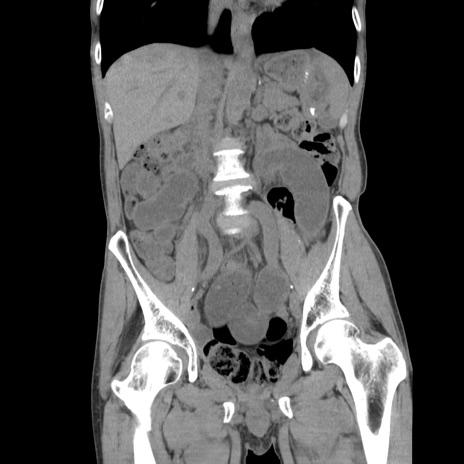

横断像